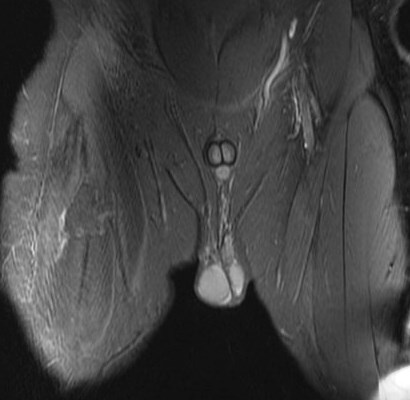

25 y/o work injury, soccer injury.

Maybe his soccer playing is his work? Who am I to ask questions. The indirect head goes on to form the central tendon. There is complete failure of the proximal myotendinous junction and there is an interposed acute hematoma. The hematoma is almost isointense to muscle. Reference article.

rectus femoris indirect head proximal myotendinous junction tear with hematoma( RID2698 )